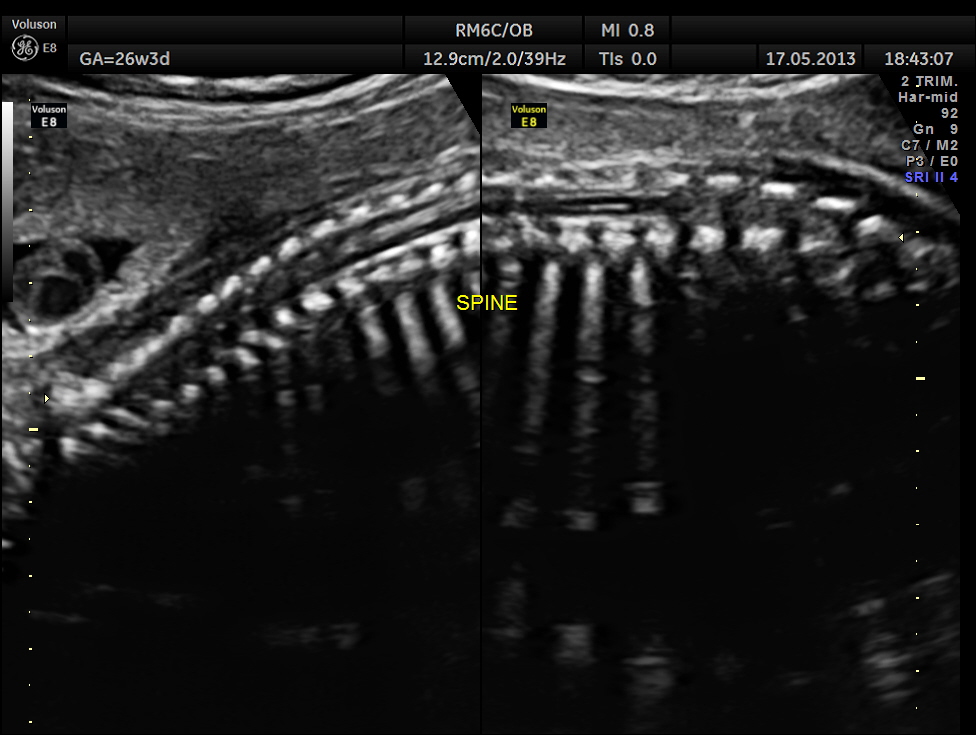

The following images show the spine.

This fetus did not show any oro-facial clefts ; heart and spine appeared normal.